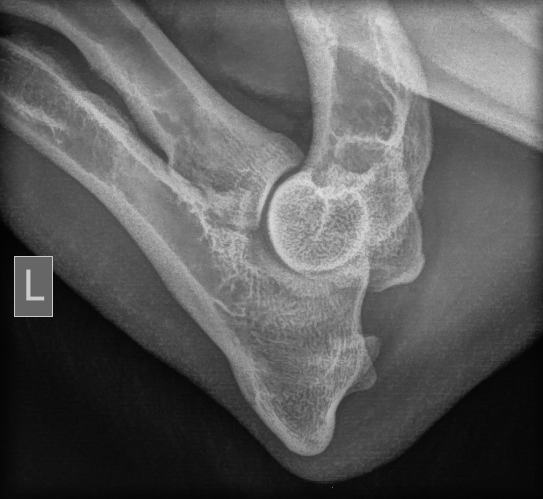

- heupdysplasie: FCI HD links B/rechts C (onder narcose aan de universiteit van Gent)

- elleboogdysplasie: FCI ED 0/0 (onder narcose)